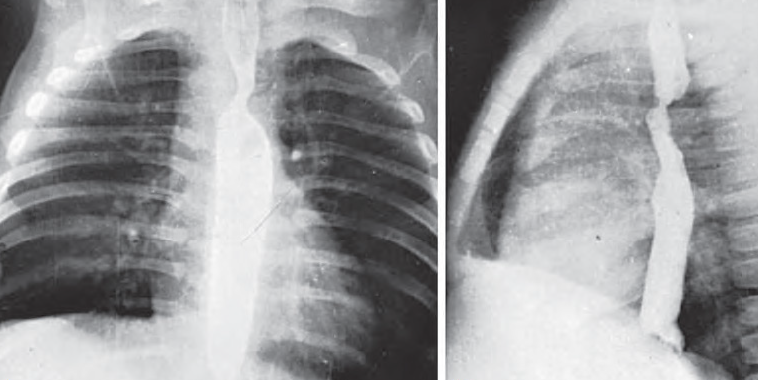

Direkt grafi ve baryumlu özefago grafide “anterior trakea basısı ve çift taraflı özefagus bası bulgusu” görülür.

Yardımcı olarak çekilen Özofagus grafisinde Posterior indentasyon görülebilir.